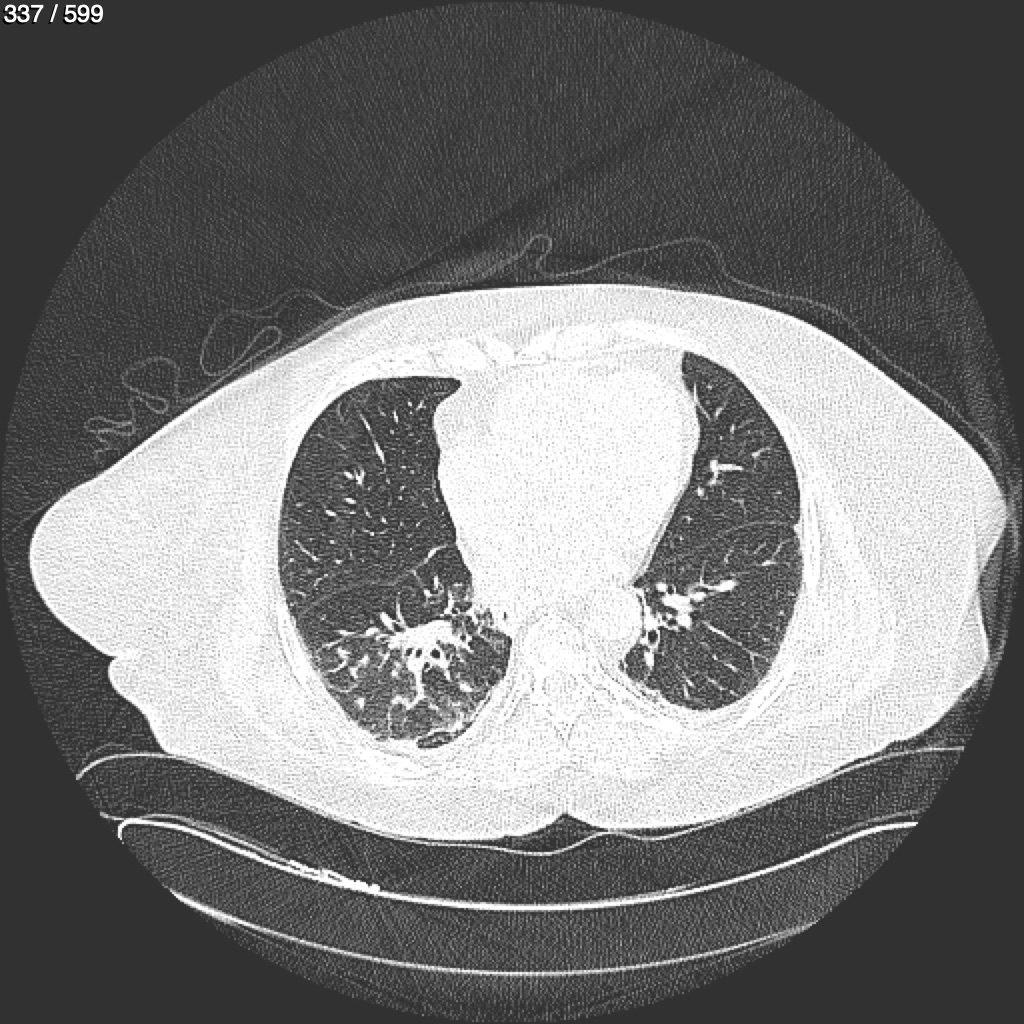

Home G​l​o​r​i​a​ ​G​l​a​d​y​s​ ​B​e​a​s​l​e​y​ ​-​ ​T​ó​r​a​x​ ​T​o​r​a​x​_​S​i​m​p​l​e​ ​(​A​d​u​l​t​o​)